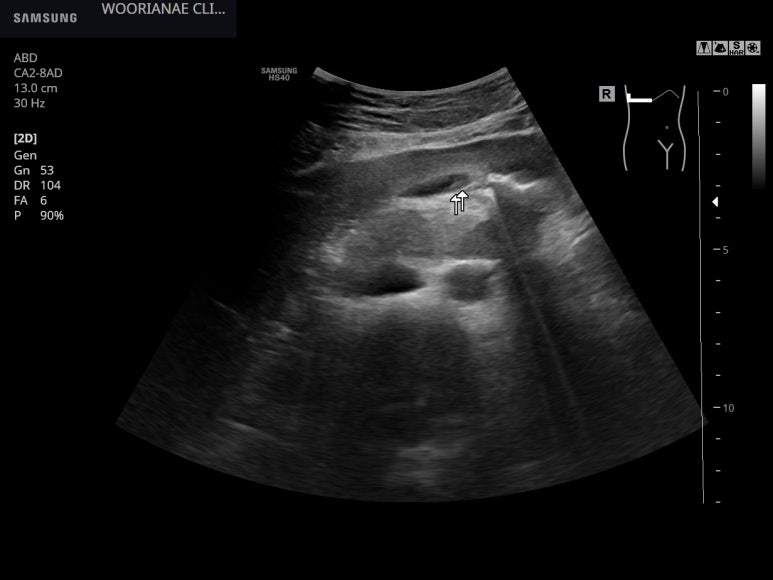

다른 의원에서 담낭 얘기를 하였기에 초음파 추적, 환자의 걱정/궁금증이 크며

공복임에도 담낭은 수축되어 있으며

내부의 음영은 자세에 따라 움직이니 담낭오니가 조금 생긴셈이다. 이차적인... 장염 및 체중감소/식사못함에 의한 결과적 소견이 의심된다.

증상적 처방에 이담제를 추가하여 10일뒤 추적

아래와 같이 담낭에 특이소견은 없다. 기존 담낭오니는 관찰되지 않으며 담낭은 수축되어 있지 않다.

이담제 등 1~2주 추가 처방 후 종료하기로 함